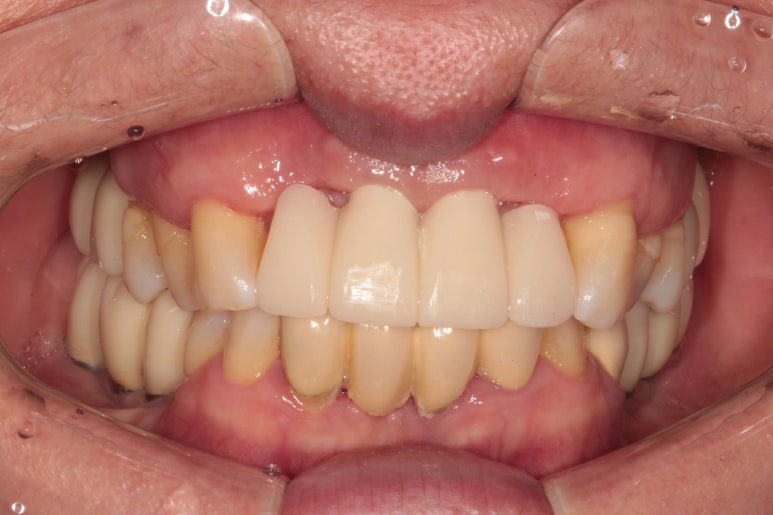

짜잔! 드디어 앞니 임플란트가 완성되었어요.

사실 저는 아래 치아와 비슷한 색으로 하고 싶었지만, 대부분의 환자분들은 도자기 같이 밝은 색이 나는걸 좋아하시죠 !!!! 지금 보시는 앞니 임플란트 보철물은 지르코니아 크라운입니다. 정확히 얘기하면 지르코니아 코어에 포세린 (도자기재질)을 붙인 PFZ 크라운입니다.

색상이 상당히 깊이가 있고, 모양도 보다 더 자연스러워진걸 보실 수 있을거에요.

신금호역 치과 백원장의 임플란트 치료의 하이라이트는 전후 비교겠죠?

최종 보철물 완성 후

아주 드라마틱한 변화를 보실 수 있을거에요!!!!

가장 우려했던 것은 고름이 나오던 치아들이 있었던 자리의 잇몸이 붕괴되면서 치아가 너무 길어지지는 않을까 하는 부분이었습니다.

그렇지만, 생각보다 조화롭게 보철물 제작이 가능하였던 것을 보실 수 있을거에요.

처음에 비하면 치석제거도 정~~~말 많이 되어 잇몸 컨디션도 아주아주 좋아진 상태입니다.